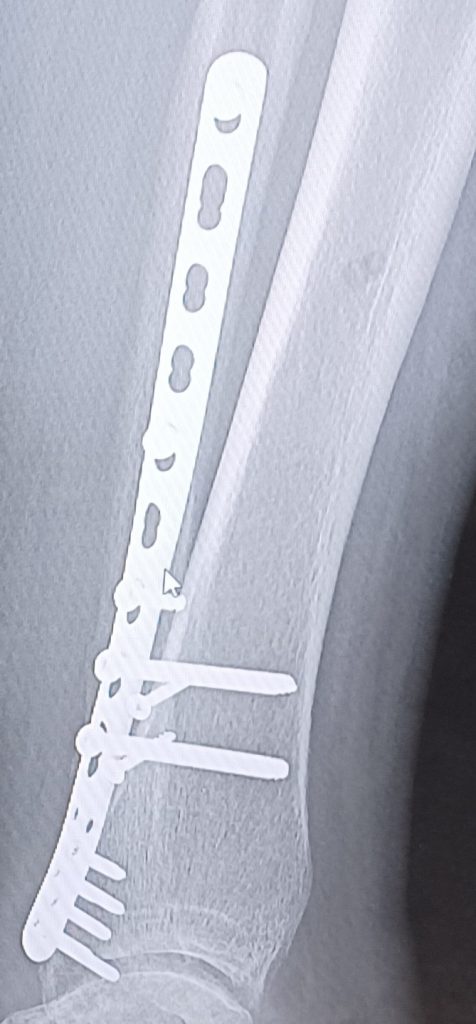

After 3 years recovered from my hip replacement surgery; Boom! Crack! Trauma! I fell and broke my knee and ankle. More specifically, a plateau fracture and a broken ankle. My tibia and fibula. Oh my goodness.

Later that night, Dr. Dvorzhinskiy came to my room to visit with me and went over my new x-rays the next day. He showed me all the hardware that was inside my ankle and knee.

I met with Dr. Dvorzhinskiy every month to follow up on my progress with healing and physical therapy. I was also amazed at the minimal pain and healing of my incisions. Dr. Dvorzhinskiy is a master surgeon and yes he played with erector sets and Legos as a child thank God lol!